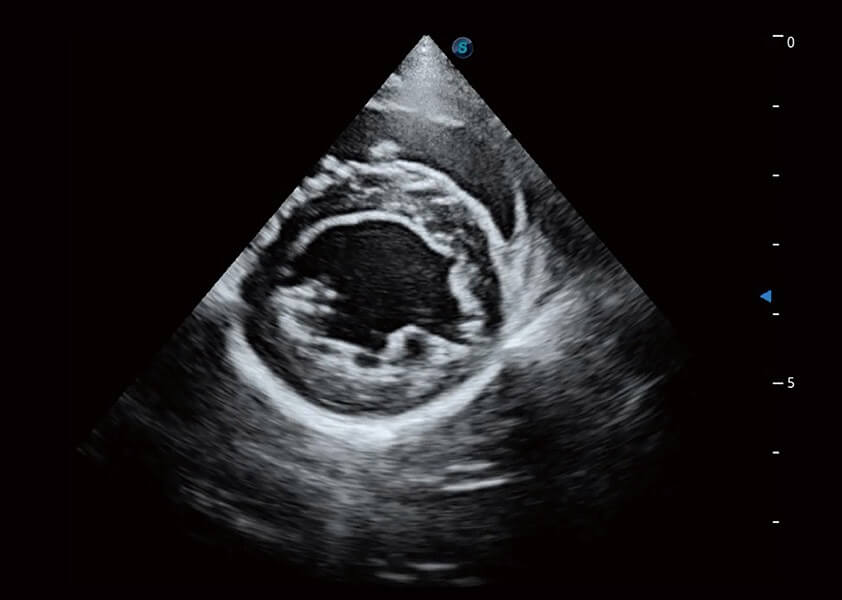

ProPet 60 作为一款高端台式动物超声设备,为动物医生的日常诊断提供了一系列贴合动物临床需求、解决临床实际问题的高级成像功能。凭借全系列高清探头,满足医生对腹部、心脏、生殖、浅表、肌骨等成像的所有需求,切实帮助您提升检查效率,提高诊断信心。

动物是人类最亲密的朋友和最值得信赖的伙伴。环球UG官网也一直致力于探索动物专用的超声影像解决方案。 全新推出的ProPet系列,是环球UG官网在动物超声影像智能化、专业化、精准化的一次跨越式革新。动物不能用言语来表述自己的不适,通过超声影像,ProPet系列搭建了动物医生与不同物种沟通的“桥梁”,为动物医生注入了“治愈之力”。